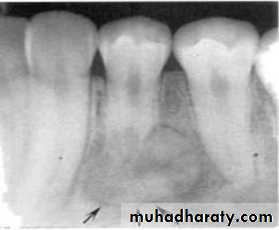

Lateral periapical cyst-well defined corticated margin

Multiple myeloma -punched out lesion